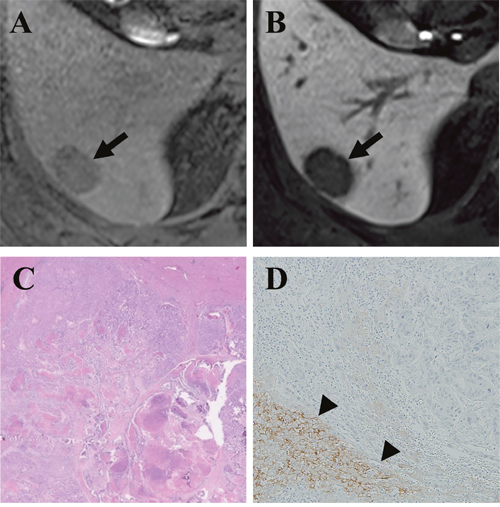

Figure 1: Gadoxetic acid-enhanced MRI of a CRLM diagnosed by surgical resection in a 61-year-old man. (A) Precontrast T1-weighted image showed a hypointense nodule (arrow) in segment 8. (B) The tumor (arrow) showed mixed hypointensity during the hepatobiliary phase (HBP) of a liver dynamic MRI. (C) Hematoxylin and eosin staining revealed grade 1 fibrosis, grade 2 central necrosis, and grade 3 cellularity. (D) Immunohistochemistry (×100) revealed weak expression of OATP1B3 (arrowhead) in 20% of the tumor.

To the best of our knowledge, no study has elucidated whether aberrant OATP1B3 proteins (which are potentially functionally defective) expressed in tumors of non-hepatocyte origin have an influence on the enhancement profile of a gadoxetic acid-enhanced MRI. Similar to previous reports that described the cytoplasmic distribution of aberrant OATP1B3 protein [21, 22], all of the CRLMs with positive OATP1B3 expression in our study showed cytoplasmic not membranous distribution of the transporter (Figure 1C). In addition, the aberrant expression of OATP1B3 was associated with mixed hypointensity of CRLMs on gadoxetic acid-enhanced MRIs in the non-chemotherapy group, which we interpret to be the result of preserved (but probably attenuated) transport function of this carrier protein. Our conclusion is compatible with the experimental data based on a colon cancer cell line, which demonstrated that aberrant OATP1B3 protein was capable of transporting several substrates - including gadoxetic acid, despite its cytoplasmic distribution [22].